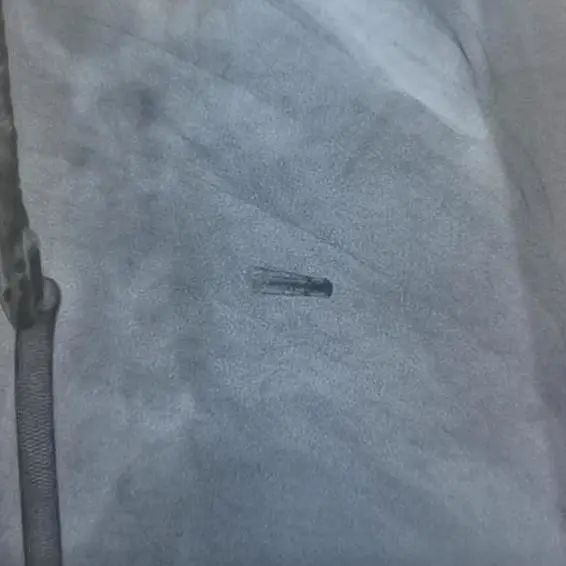

DragonFly二尖瓣瓣膜夹释放